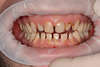

1- Les couronnes pour restaurer des dents usées et cariées

Il est possible de corriger des situations pathologiques liées à une usure importante des dents.